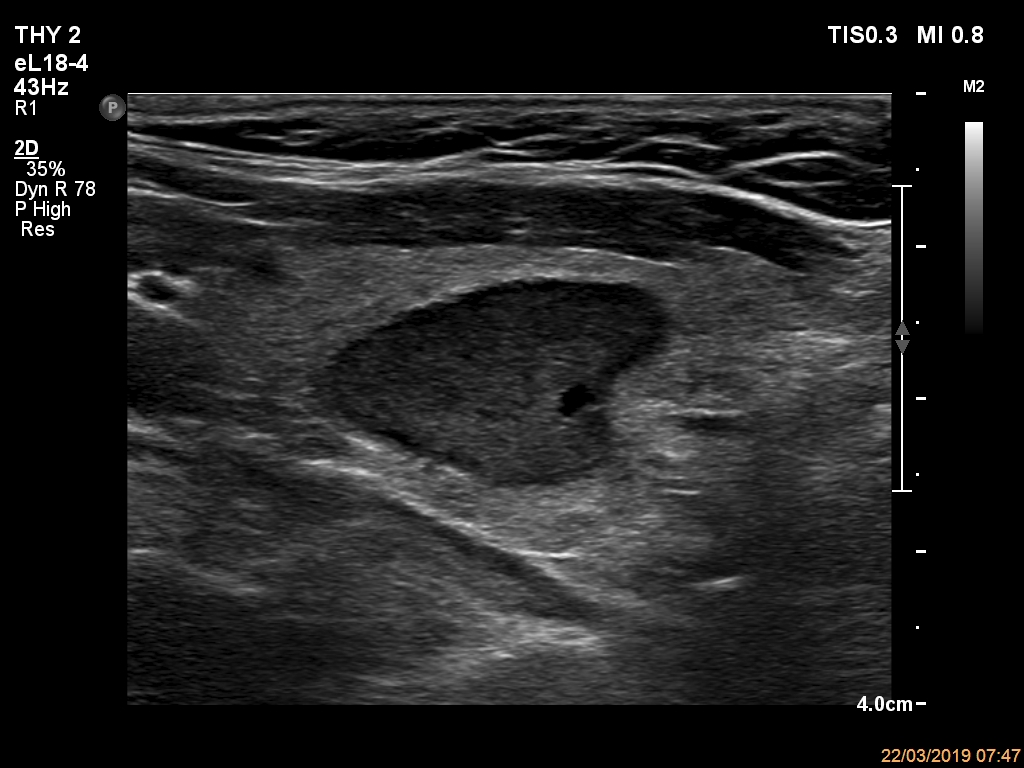

Ultrasonography. The thyroid was echonormal and had multiple nodules. The only lesion of a possible oncological importance was in the left lobe. It was hypoechoic. The dimensions were 16x14x23 mm (width, depth, length, respectively). The lower border presented an undulation which was caused by another, hyperechoic nodule. The nodule presented a predominant perinodular blood flow and had an average rigidity on elastography.

The nodule in the left lobe illustrates non-pathological form of lobulated margins.